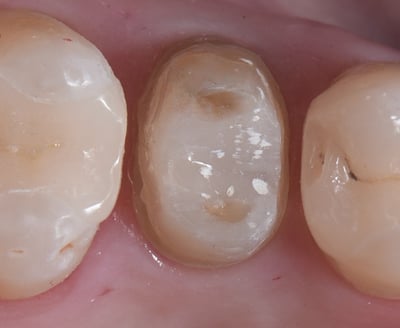

Hechten van de partiële restauraties aan de eerste, bovenste |

Preparatie van de marginale randen aan de bovenste, tweede |